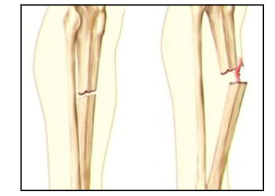

What are the two types of fractures? Describe them

Simple fracture: Just bone

Compound fracture: Bone pierces into skin

What type of fracture is this?

Greenstick fracture

Prone in young children

Epiphyseal fracture

more common in younger age